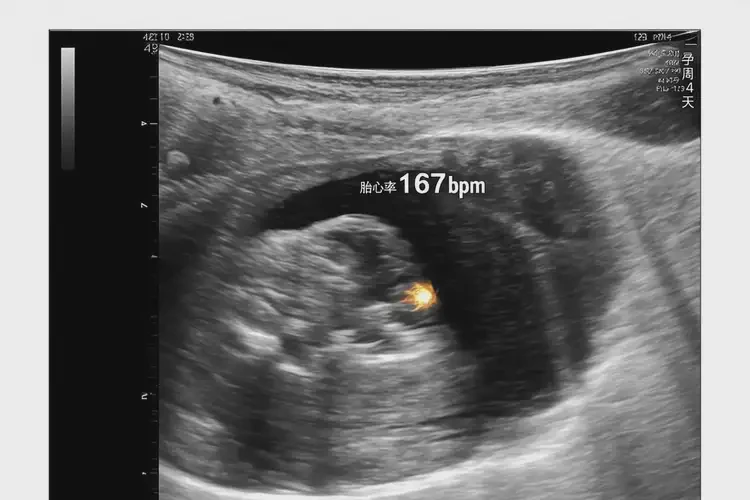

孕6周4天胎心167正常嗎

167次/分鐘

在孕6周4天時(shí),胎心率達(dá)到167次/分鐘是 正常 的。胎心率通常在懷孕早期較快,隨著孕周增加會(huì)逐漸減慢。以下是詳細(xì)解釋:

孕6周4天胎心167正常嗎(圖1)